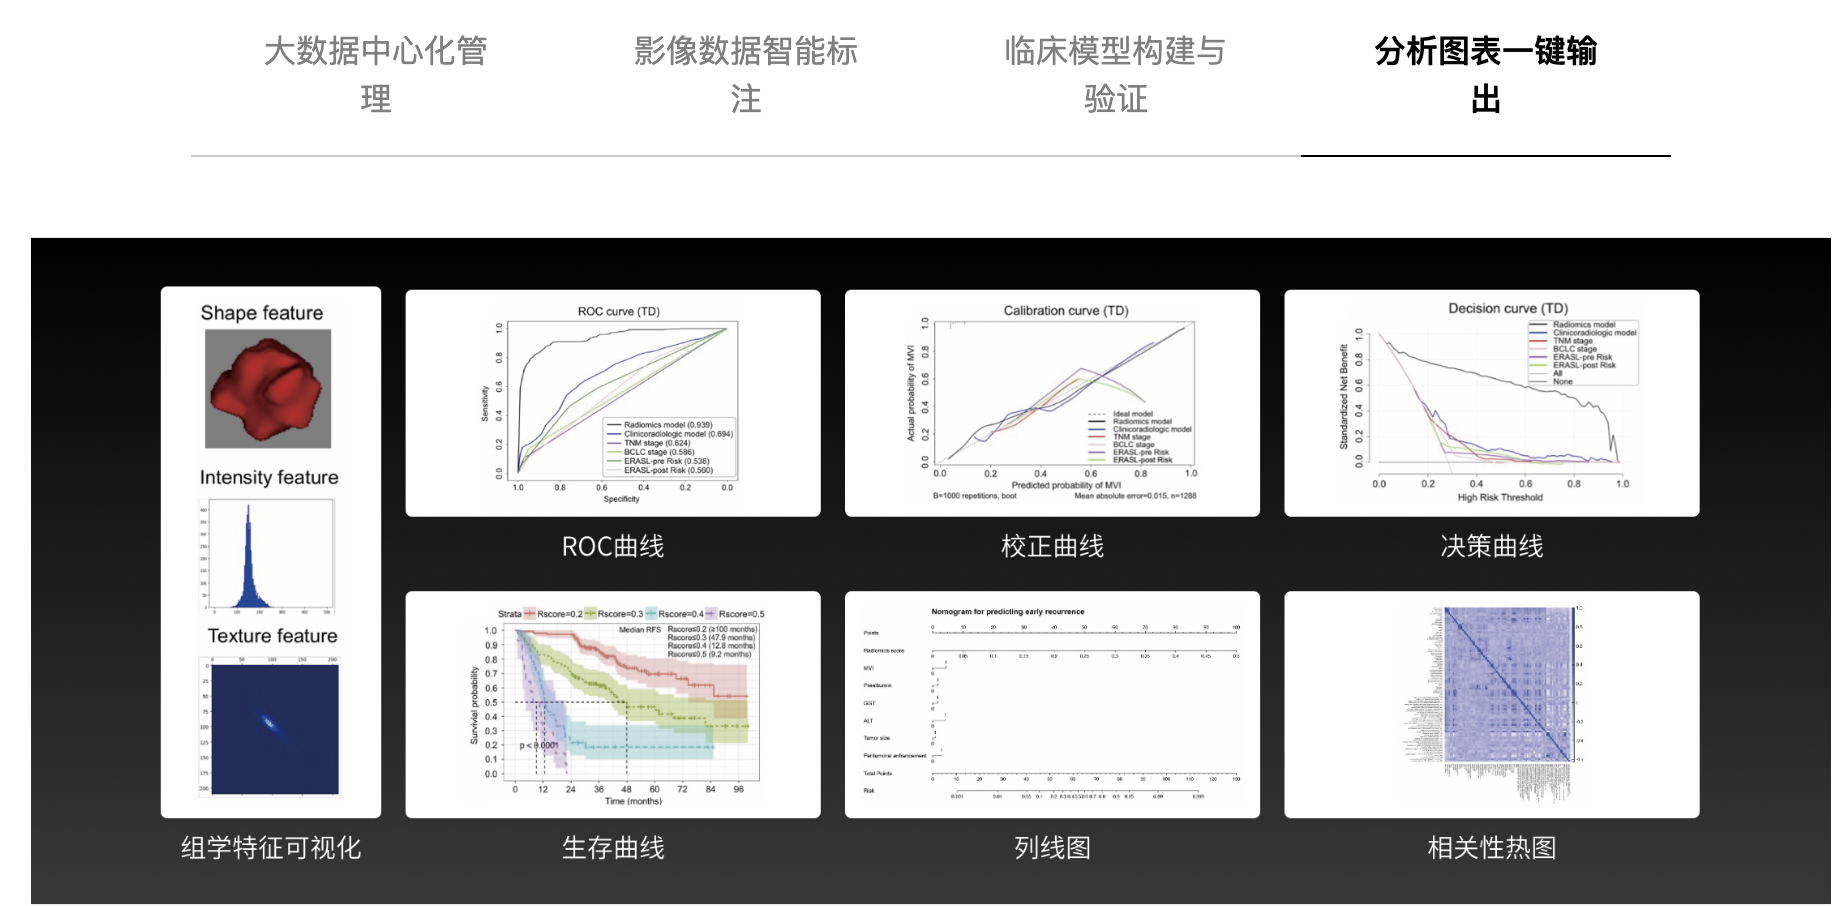

打通从临床大数据管理、智能数据标注、3D图像渲染、影像组学分析、到深度学习模型训练和统计分析结果输出的一站式科研全流程。

影像组学模块:在组学模块中包含三个子模块:特征提取、特征选择以及机器学习模型的训练。特征提取是在ROI区域提取图像相关的统计特征;特征选择是在特征提取的基础上做相关性分析;机 器学习模型的训练是在特征提取以及特征选择的基础上做相关分类、回归。

最后举一个用该平台发表SCI的论文,感兴趣的可以看一看。